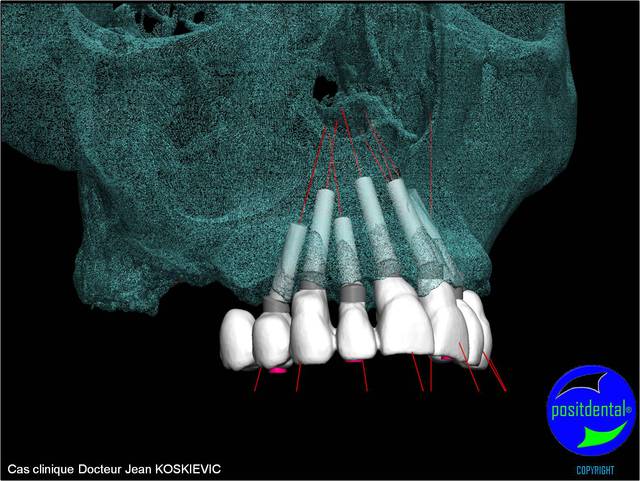

rendu 3D maxillaire sup, pano et photo

Mci - Eugenol